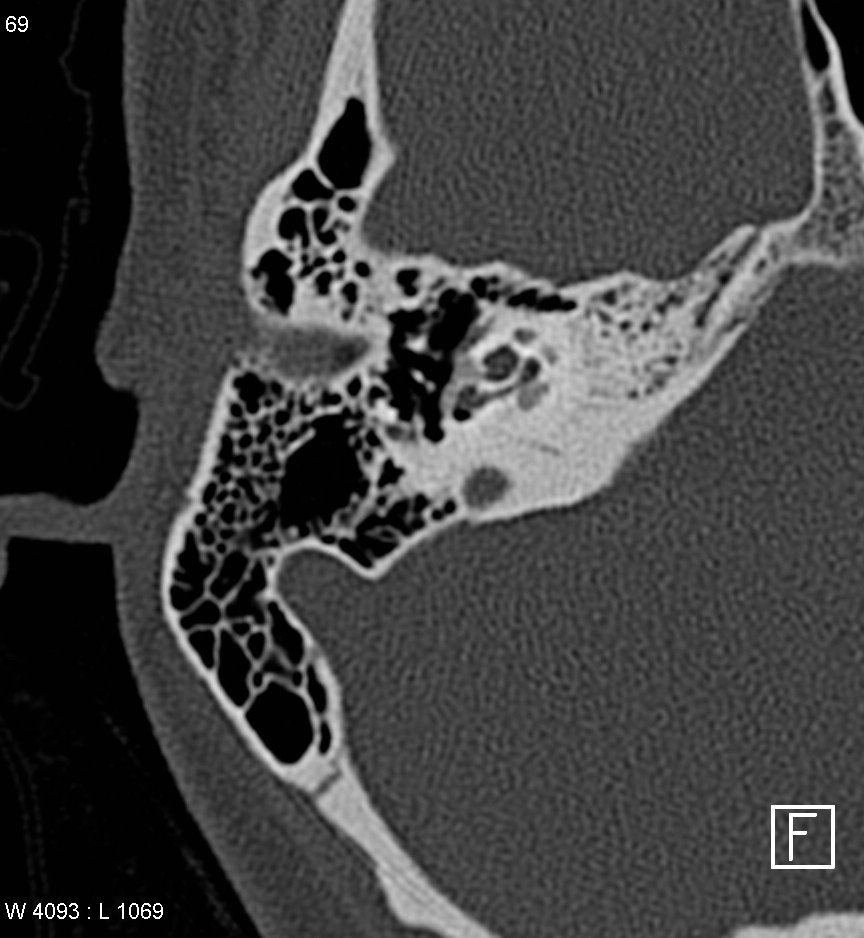

cochlear aplasia

The labyrinth is abnormal with the cochlear absent (cochlear aplasia). The vestibule, semicircular canals and ossicles are present.

Cochlear aplasia, or complete absence of the cochlea is a rare anomaly which accounts for only 3% of cochlear malformations.